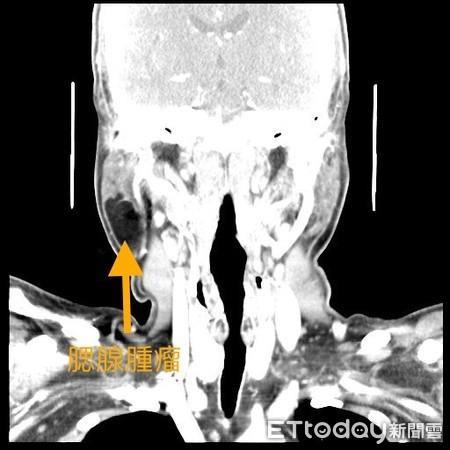

台南市立安南医院耳鼻喉科刘金瑞医师说,腮腺炎超过4周可能为肿瘤警讯,要注意。(图/记者林悦翻摄)

30几岁王先生,因左侧耳下一颗肿瘤1年多来门诊求诊,偶尔会特别肿胀,有时又会稍微比较小,没有明显的疼痛感,但肿瘤的体积比起愈来愈大,不只影响外观也轻微影响到他咀嚼食物时的功能,安南医院耳鼻喉科刘金瑞医师说,超过4周可能为肿瘤警讯。

刘金瑞医师说,上述案例其实在耳鼻喉科门诊并不少见,这个位置的肿瘤,有些医师会误认为是民间俗称的「猪头皮」,正确名称为「腮腺炎」的疾病。腮腺炎本身是一种病毒性的传染疾病,但一般在1到2周内就可缓解,若病患肿瘤在耳下或耳前位置超过4周,一般就要高度怀疑是否为唾液腺肿瘤。

刘金瑞表示,人体本身有3对大唾液腺分别为腮腺、下颌腺及舌下腺,而这些唾液腺都有可能长出肿瘤,但以位于腮腺的肿瘤最棘手。因为腮腺本身位置正好是掌管脸部表情肌肉的颜面神经会经过的位置。若在外科手术的情形下伤害到这条神经,有可能造成病患的嘴角歪斜、眼睛无法闭合甚至最终失明及单边颜面肌肉完全麻痹等后遗症。因此对于病患及医师来说都是个具有高度压力及难度的手术。

刘医师指出,腮腺肿瘤大体可区分为良性及恶性,一部分的良性肿瘤也可能在时间的变化下有癌变的机率,因此在临床上看到这类病患,通常建议及早手术将其移除。一方面是在肿瘤体积小的时候对外观的影响较小且开刀时伤害到颜面神经的机会也较小。